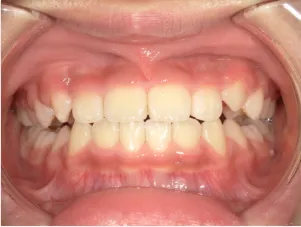

治療前①小1(7y2m):初診

*上顎前歯後方傾斜、上下唇の突出、口唇閉鎖不全傾向、コンケーブなし

| カウンセリング・診断結果 | 骨格的に下顎前方位で下顎骨も大きいタイプで、上の前歯が後ろに傾斜している受け口です。 顔立ちは上下唇が突出していて口唇閉鎖不全傾向がありますが、コンケーブにはなっていません(写真①)。 機能的に低位舌があり、今後受け口を助長する可能性があります。 受け口は、上顎骨の骨格的な前方向の成長を阻害し下顎が前へ強く成長していくため、骨格的な受け口が悪化し永久歯の咬合治療が難しくなり、症例によっては外科的な治療が必要になることがあるため早期に改善し骨格的な悪化を予防する説明をしました。 |